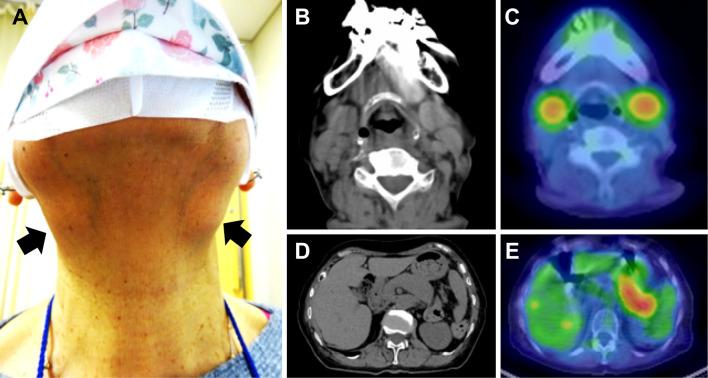

A 78-year-old Japanese woman with no history of rheumatic disease received 2 doses of the BNT162b2 COVID-19 mRNA vaccine. Two weeks later, she noticed bilateral swelling in the submandibular region. Blood tests showed hyper-immunoglobulin (Ig)G4emia, and F-fluorodeoxyglucose (FDG)-positron emission tomography (PET) revealed the strong accumulation of FDG in the enlarged pancreas. She was diagnosed with IgG4-related disease (IgG4-RD) according to the American College of Rheumatology (ACR)/the European League Against Rheumatism (EULAR) classification criteria. Treatment was started with prednisolone at 30 mg/day, and the organ enlargement improved. We herein report a case of IgG4-RD that may have been associated with an mRNA vaccine.

一位 78 岁的日本女性,既往无风湿病史,接种了两剂 BNT162b2 COVID-19 mRNA 疫苗。两周后,她注意到双侧下颌下区域肿胀。血液检查显示高免疫球蛋白(Ig)G4 血症,氟-18 脱氧葡萄糖(FDG)正电子发射断层扫描(PET)显示 FDG 在肿大的胰腺中强烈积聚。根据美国风湿病学会(ACR)/欧洲抗风湿病联盟(EULAR)分类标准,她被诊断为 IgG4 相关疾病(IgG4-RD)。开始用泼尼松龙 30 mg/天治疗,器官肿大得到改善。我们在此报告一例可能与 mRNA 疫苗相关的 IgG4-RD 病例。